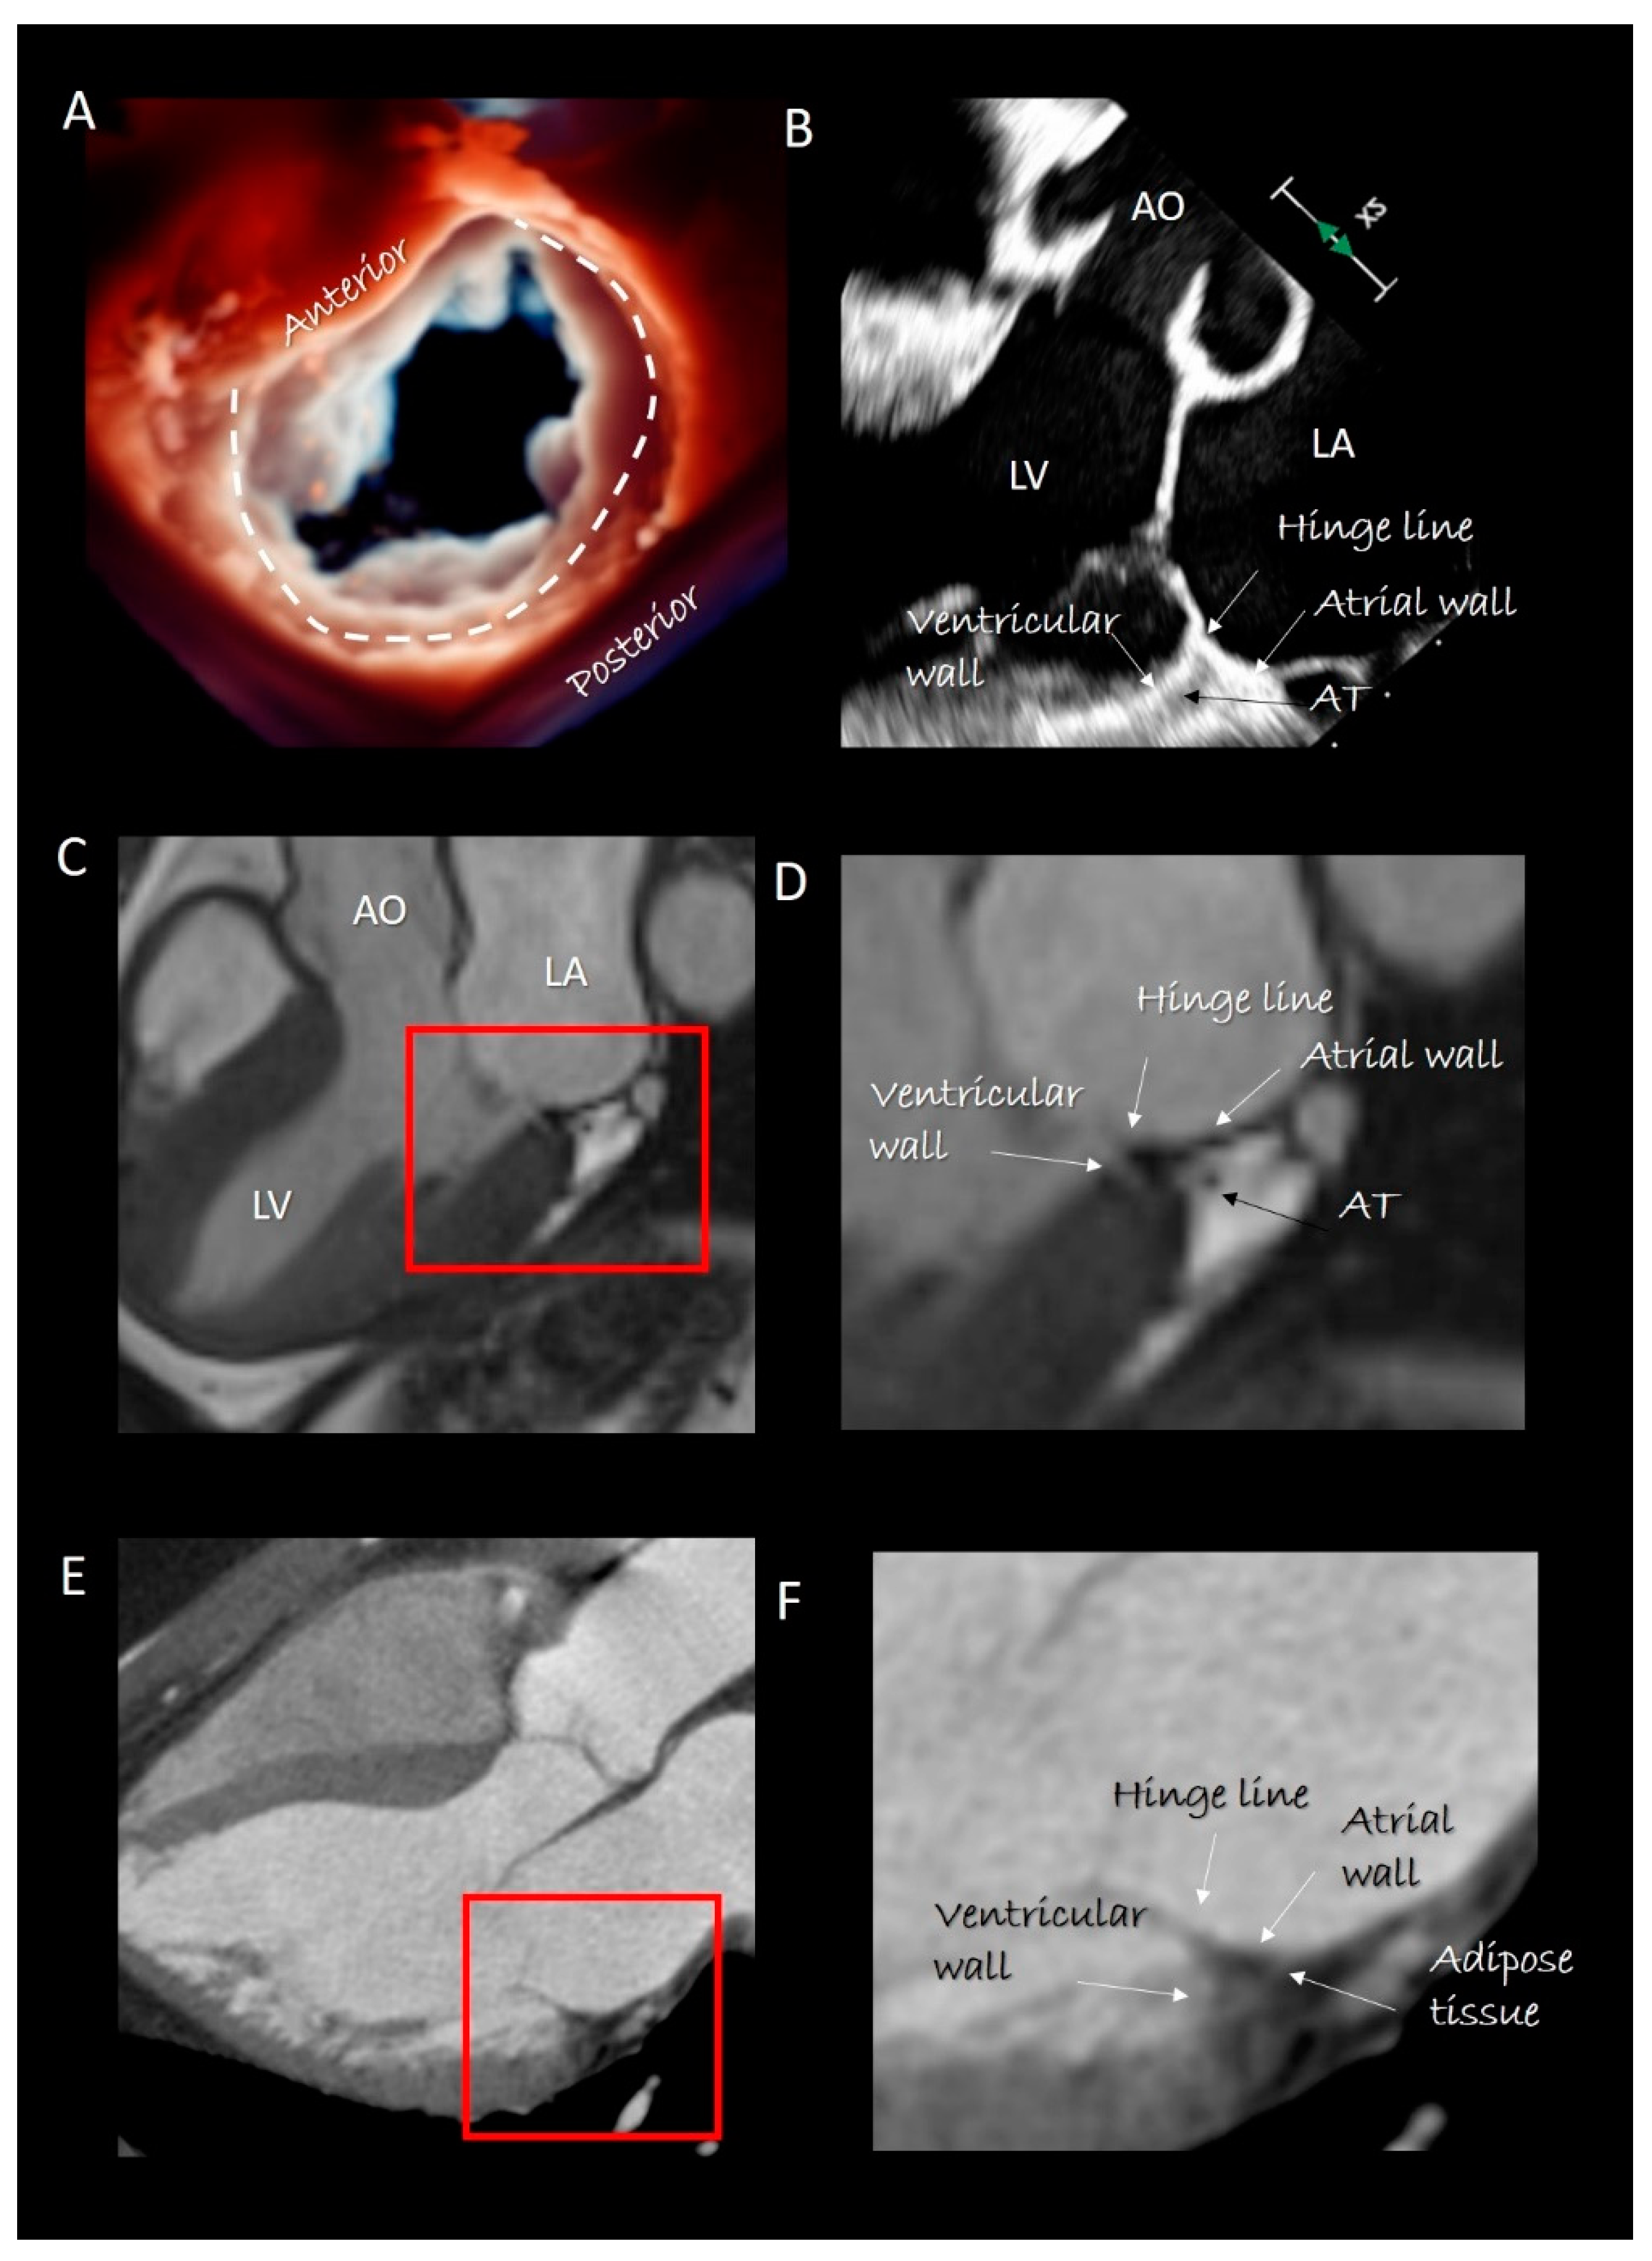

2. Mitral Annulus

Imaging Techniques

6.1.3. MA Disjunction